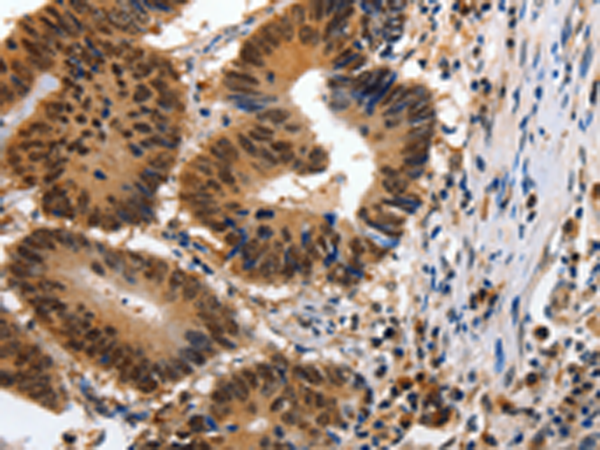

分类: 科研抗体货号: P11052别名: HS1, GW128, YWHAA, KCIP-1应用: WB,IHC反应种属: Human, Mouse, Rat